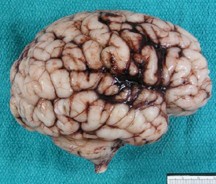

Macroscopy

- most useful in acute cases

- subdural and subarachnoid hemorrhages usually thin

- germinal matrix hemorrhage located in the anterior ganglionic eminence over the caudate, often unilateral and asymmetric, associated with IVH

- hemorrhagic conversion of ischemic lesions more bilateral and symmetric in posterior white matter

- IVH seldom due to extension of white matter hemorrhage

- large intraventricular blood degrades slowly

- progresive hydrocephalus in 20%

- lateral extension of germinal matrix hemorrhage can damage maturing brain parenchyma

- resolution of the hematoma (few months) results in focal, smooth-walled cyst adjacent to lateral ventricle